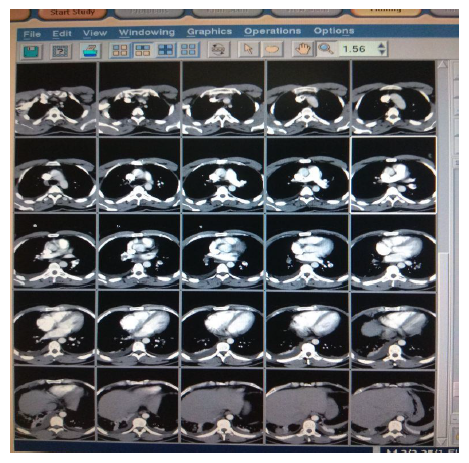

The patient was admitted to the ward and treated with IV antibiotics, analgesics, antipyretics, and oxygen therapy. Computed Tomography (CT) Chest (Figure 2) showed peripheral patchy areas of consolidation/atelectasis-like changes in the right middle, right lower lobes, and left lower lobe. It also shows the patient's lead Electrocardiogram (ECG), showing right ventricular strain (S1Q3T3 pattern), with mild T wave inversions in anterior leads.

Figure 2 Lead ECG